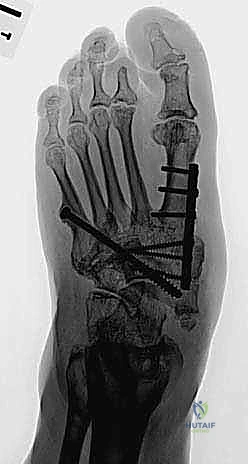

هذه هي المرحلة الأهم، حيث يتم دمج العظام المتضررة معاً لتكوين كتلة عظمية صلبة ومستقرة. يعتمد الدكتور هطيف على تقنيتين رئيسيتين حسب حالة المريض:

أ) التثبيت الداخلي الشديد (Superconstruct Internal Fixation):

استخدام صفائح معدنية سميكة جداً ومسامير طويلة (أقوى من تلك المستخدمة في الكسور العادية) لتثبيت العظام الهشة. يتم وضع هذه الدعامات داخل القدم لتكوين هيكل جديد.

ب) التثبيت الخارجي الحلقي (جهاز إليزروف - Ilizarov Apparatus):

يُعد الأستاذ الدكتور محمد هطيف من أبرز الخبراء في استخدام جهاز إليزروف في اليمن. يُستخدم هذا الجهاز عندما تكون جودة العظام سيئة جداً أو في حالة وجود التهاب أو قرحة مفتوحة تمنع وضع معادن داخلية. عبارة عن حلقات معدنية تحيط بالقدم والساق، متصلة بأسلاك دقيقة تخترق العظام، مما يوفر ثباتاً ميكانيكياً هائلاً ويسمح للمريض بالمشي التدريجي أثناء فترة الالتئام.